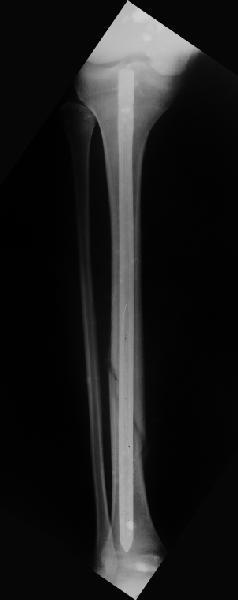

Вчера первый раз синтезировали голень гвоздем Fixion.

Спиральный оскольчатый перелом, ниже середины, у молодого парня. Сделали "классический" вариант гвоздя, который еще без винтов. Получилось все легко. Не торопясь, сделали операцию минут за 20. См. фото.

В отношении ранней нагрузки при спиральных переломах лучше не торопиться. По данному случаю необходимо достигнуть исчезновения щели между штифтом и внутреним кортексом по Rg. А так картинка прекрасная - и длина сегмента и репозиция. Можно поздравить, коллега!

Да, спасибо за интересные иллюстрации. Получилось очень симпатично. На большеберцовой кости непременно надо было винты? Там же был торцовый упор, перелом в средней трети?